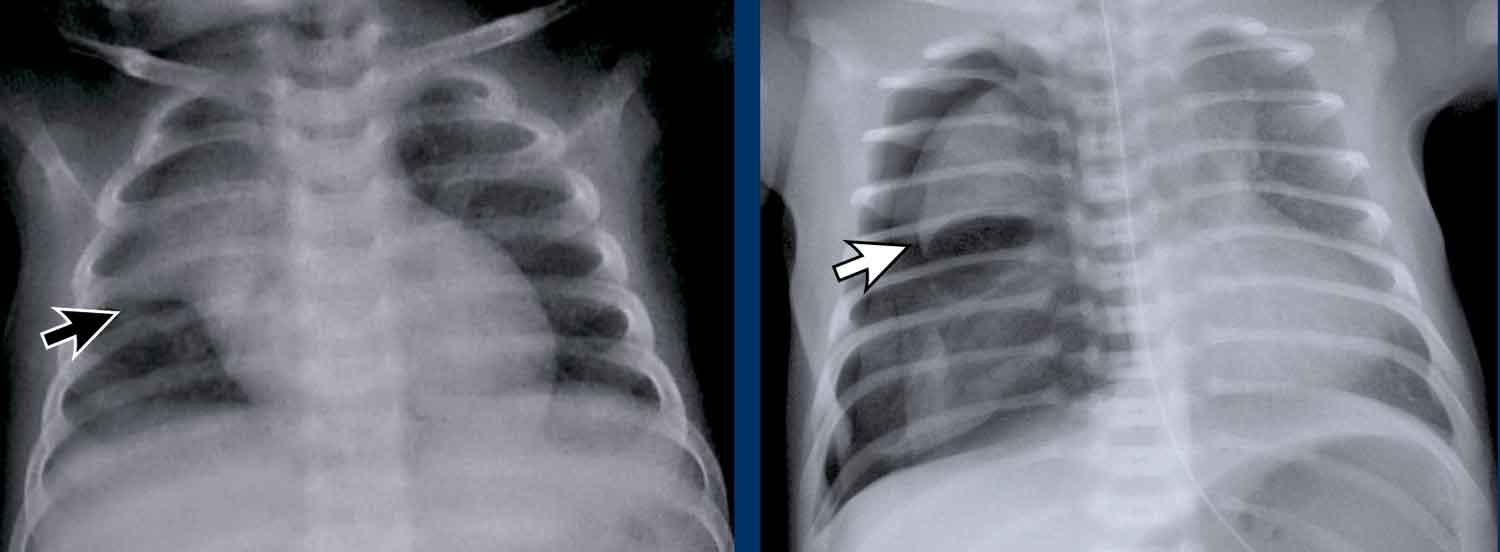

Đây là hình ảnh của một nam giới 24 tuổi.

Hãy quan sát kỹ các hình ảnh trước.

Câu hỏi: đây có phải là tuyến ức bình thường không?

Hình ảnh

Mặc dù tuyến ức này khá lớn, nhưng có hình tam giác bình thường và chứa mỡ (mũi tên).

Đây là tuyến ức bình thường.